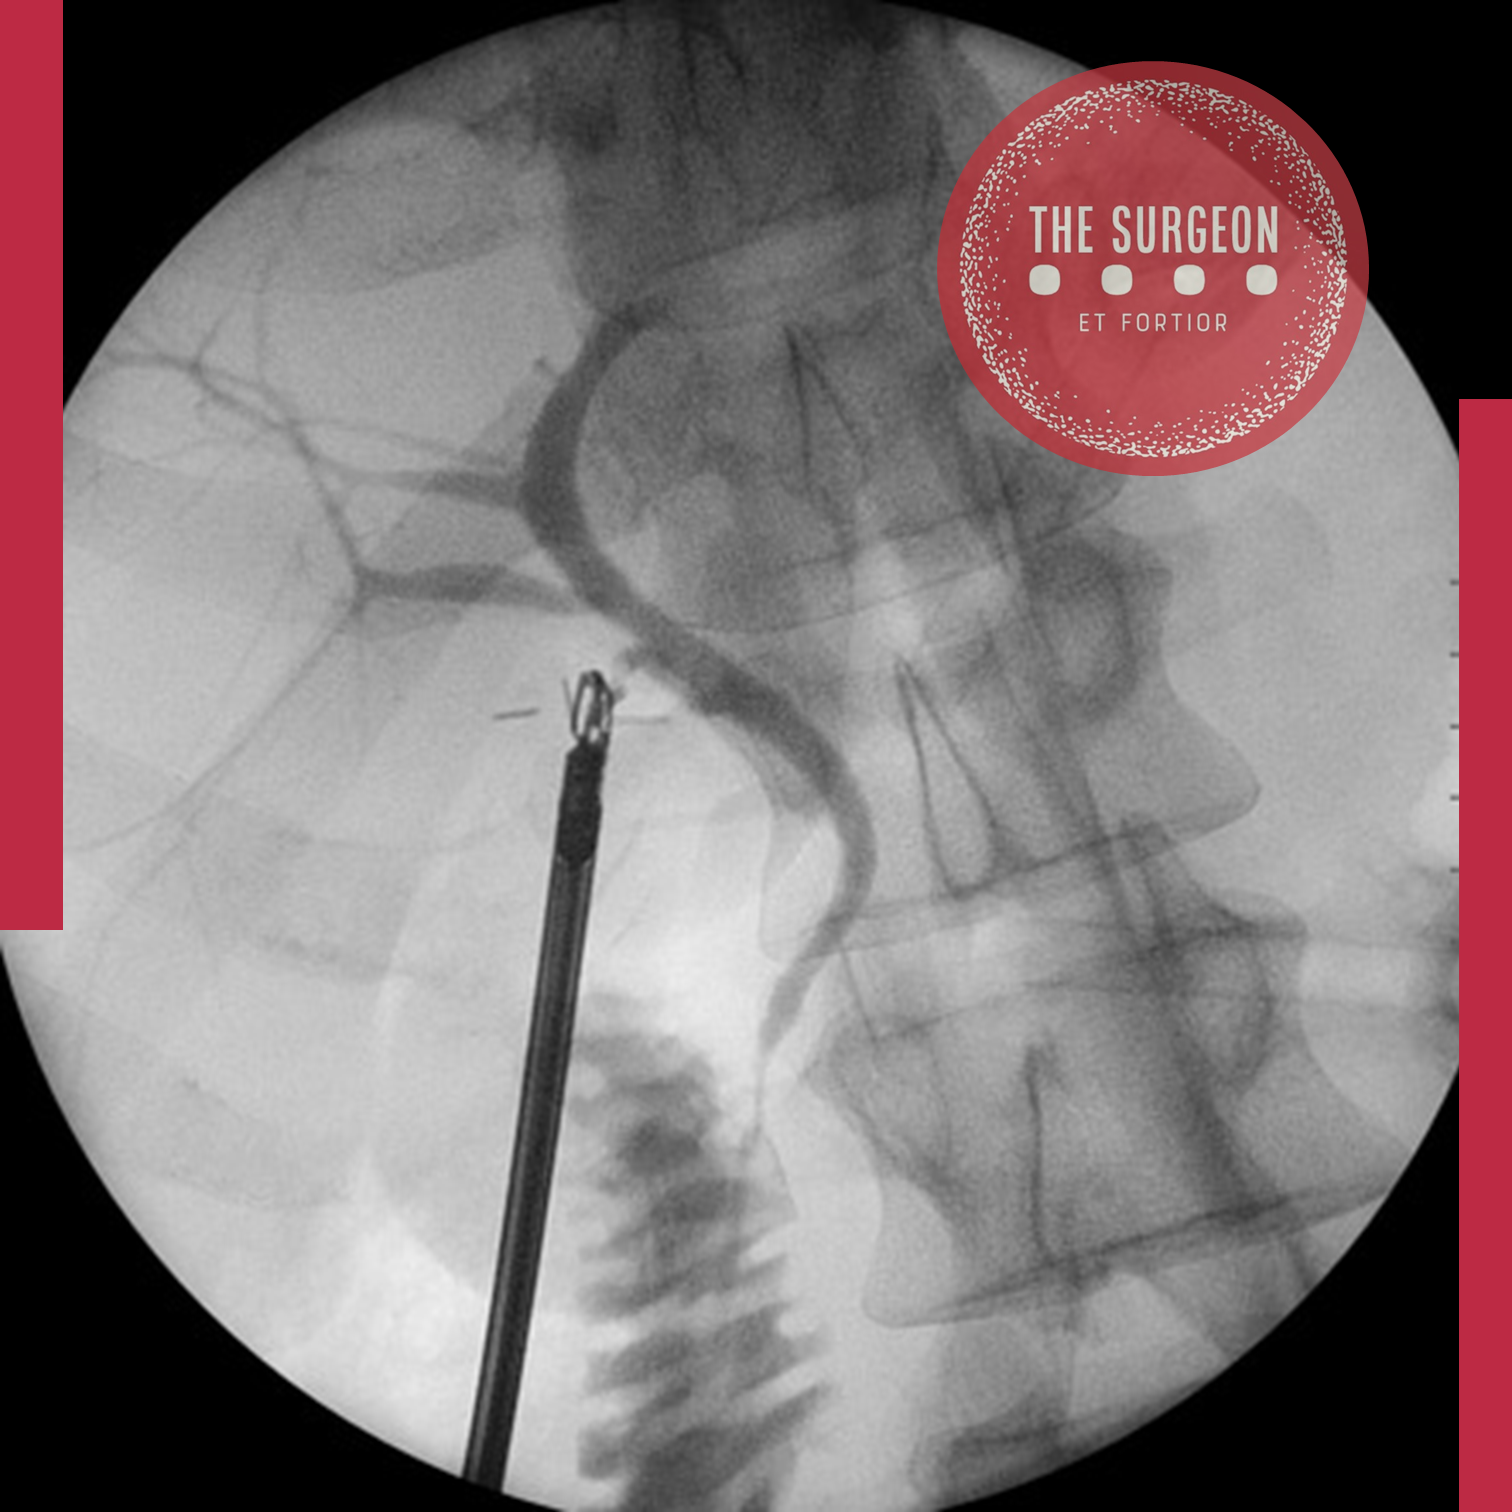

Outro método de identificação conclusiva das estruturas císticas é a colangiografia intraoperatória rotineira. Vários estudos prospectivos tentaram avaliar a utilidade da colangiografia intraoperatória na prevenção de lesões do ducto biliar comum. Uma meta-análise de 40 séries de casos detalhando 327.523 colecistectomias laparoscópicas e 405 lesões maiores foi realizada em 2002. A taxa de lesão foi reduzida pela metade no grupo de colangiografia intraoperatória rotineira (0,21%) em comparação com o grupo seletivo (0,43%). Além disso, no grupo seletivo, apenas 21,7% das lesões do ducto biliar comum foram detectadas intraoperatoriamente. Fletcher et al. descobriram que a colangiografia intraoperatória rotineira reduziu a incidência de lesão. No entanto, outros estudos sugerem que a gravidade, mas não a incidência de lesões biliares, é reduzida pela colangiografia intraoperatória rotineira.